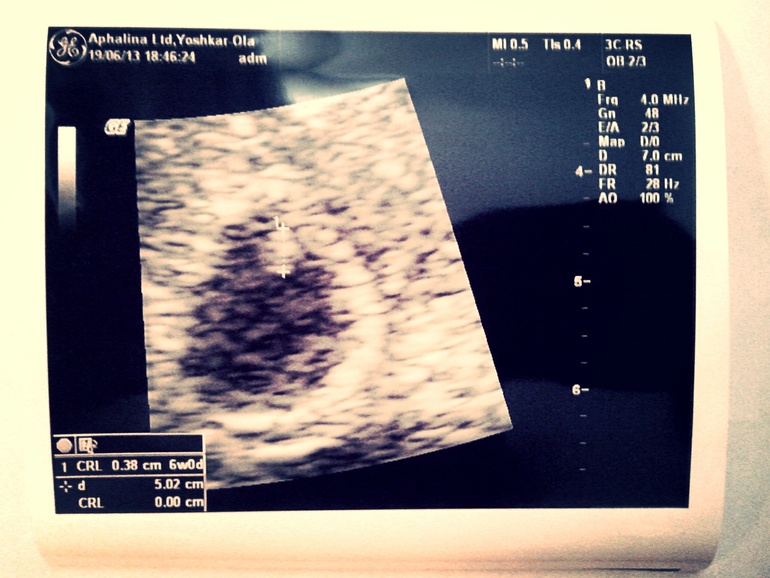

Наше первое УЗИ:)))

Ксюша, ну и чего ты решила с сохранением? И еще вопрос, скажи плиз, врач не говорила тебе, что КТР 3,8 для 6 недель маленький? У моей табличка безжалостная, там сказано что должно быть уже 5мм.

че вот вы меня еще больше пугаете? У кого то на 6 неделях вообще эмбрион не видно, у девушки с моим сроком тоже такой же, если не меньше. Врач мой сказал, что норма, 6 недель же акушерских, а от зачатия 4. Я щас пришла ложиться в больницу, сижу, жду.

у меня на сроке 6н5д=5,4 а вот с дочкой был на 7н=5.2 так что думаю всё ок!